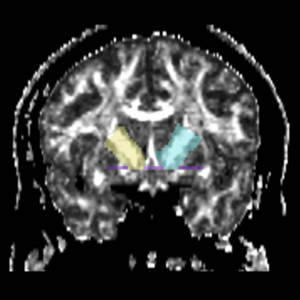

Cingulum Bundle

Interconnects limbic structures (DLPFC, cingulate gyrus, parahippocampal gyrus). Involved in attention, emotions, spatial orientation, memory. Abnormalities here could be related to negative symptoms, hallucinations, memory and executive attentional deficits in schizophrenia.

Tractography - 4 ROIs define Connectivity - Orbital frontal cortex to amygdala

Cingulum

ROI 1) A coronal plane in the most anterior point of the corpus callosum was selected using the mid-saggital plane (Fig.18), and the left and right ROI1s were drawn on the superior side of the corpus callosum (Fig.15)

ROI 2) & ROI 3) The first coronal slice where the left and right corpus connect was selected: the left and right ROI2s were drawn on the superior side of the corpus and the left and right ROI3s were drawn on the inferior side of the corpus (Fig. 16 & 18)

ROI 4) The first coronal slice showing where the middle cerebellar peduncle was slected, and the left and right ROI4s were drawn(Fig. 17 & 19)

Figure 15. Coronal View of Cingulum Bundle ROI 1, Left and Right

Figure 16. Coronal View of Cingulum Bundle ROI's 2 & 3, left and right

Figure 17. Coronal View of Cingulum Bundle ROI 4, left and right

Figure 18. Cingulum Bundle ROI's 1, 2, and 3

Figure 19. Cingulum Bundle ROI 4

The color coding of the resulting ROIs is as follows:

ROI 1: Left(7) - Right(8)

ROI 2: Left(9) - Right(16)

ROI 3: Left(11) - Right(12)

ROI 4: Left(13) - Right(14)